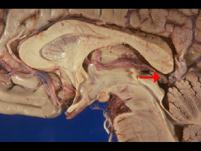

如图箭头所示为大脑哪个部位 ( )A、松果体B、中脑导水管C、后连合D、四叠体E、中脑顶盖

选项 A、松果体 B、中脑导水管 C、后连合 D、四叠体 E、中脑顶盖

答案 A